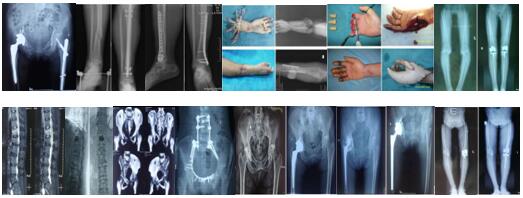

术后影像学资料如下:

骨盆骨折多由高能量损伤所致,多伴有合并症或多发伤,处理棘手,致残率高达50%~60%。经过孟泽祖主治医师、李鹏鹏住院医师的精心管理与辛勤付出,患者曹某腰椎骨折术后病情恢复良好。于2020年4月1日在全麻下行骨盆粉碎性骨折切开复位内固定术,患者多处骨盆粉碎性骨折,病情复杂,手术时间长,术中出血多。首次采用改良stoppa+右髂后上棘联合入路,手术顺利,术后病情不稳定,经过主管医师孟泽祖与全科骨干医师、护士的通力合作与坚守,术后病情日趋稳定。复查下肢血管超声提示:未见明显血栓。患者曹某在我院经过标准化、专业化的综合治疗后,患者病情恢复良好,神经损伤症状已基本恢复,伤口I级愈合,患者带着满意的笑容康复出院了。